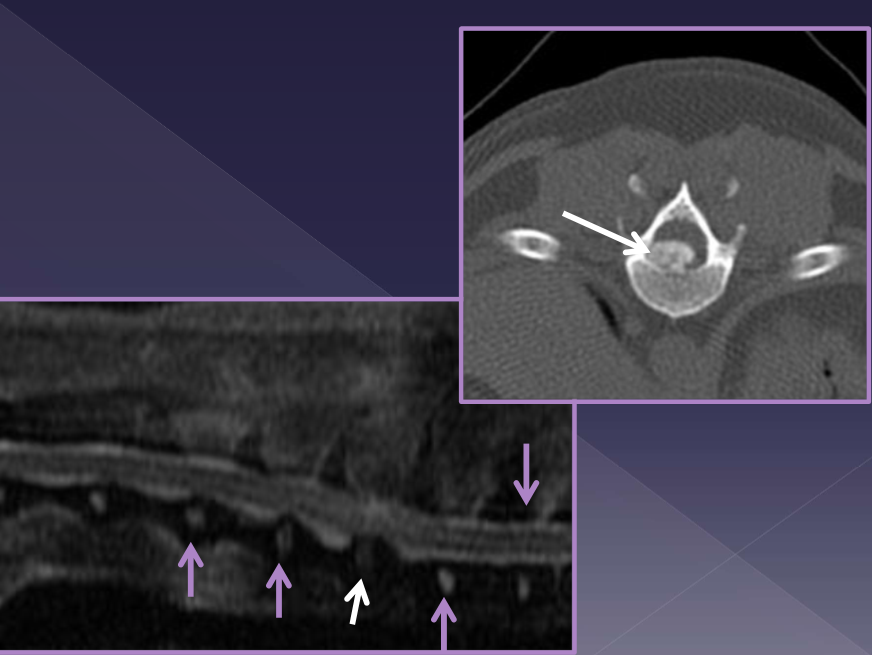

wobbler syndrome

cervical malformation or cervical protrusion →

compression of spinal cord / nerve roots →

pain and neurologic deficits

vertebral canal is proportionally smaller

dynamic and static disease

disc-associated vs osseous-associated compression

Disc-associated wobbler syndrome

middle-aged, large breed dog

Doberman pinscher*

vertebral canal stenosis (C5-6,6-7)

diagnosis

radiographs - limited information not helpful

CT -better for bone

traditional method

identify direction of compression

MRI * soft tissue better

gold standard

more accurate at identifying site, severity, nature of compression

assessment of spinal cord parenchyma

sometimes have to do MRI and CT